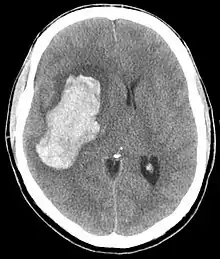

| CT scan depicting intracranial hemorrhage, a possible complication of hypertensive emergency. Patients with spontaneous intracranial hemorrhage present with newfound headache and neurologic deficits. | |

The most common presentations of hypertensive emergencies are cerebral infarction (24.5%), pulmonary edema (22.5%), hypertensive encephalopathy (16.3%), and congestive heart failure (12%).[4] Less common presentations include intracranial bleeding, aortic dissection, and pre-eclampsia or eclampsia.[5]

In the brain, hypertensive encephalopathy - characterized by hypertension, altered mental status, and swelling of the optic disc - is a manifestation of the dysfunction of cerebral autoregulation. Cerebral autoregulation is the ability of the blood vessels in the brain to maintain a constant blood flow. People with chronic hypertension can tolerate higher arterial pressure before their autoregulation system is disrupted. Hypertensives also have an increased cerebrovascular resistance which puts them at greater risk of developing cerebral ischemia if the blood flow decreases into a normotensive range. On the other hand, sudden or rapid rises in blood pressure may cause hyperperfusion and increased cerebral blood flow, causing increased intracranial pressure and cerebral edema, with increased risk of intracranial bleeding.[6]

Consequences of hypertensive emergency result after prolonged elevations in blood pressure and associated end-organ dysfunction. Acute end-organ damage may occur, affecting the neurological, cardiovascular, kidney, or other organ systems. Some examples of neurological damage include hypertensive encephalopathy, cerebral vascular accident/cerebral infarction, subarachnoid hemorrhage, and intracranial bleeding. Cardiovascular system damage can include myocardial ischemia/infarction, acute left ventricular dysfunction, acute pulmonary edema, and aortic dissection. Other end-organ damage can include acute kidney failure or insufficiency, retinopathy, eclampsia, lung cancer, brain cancer, leukemia and microangiopathic hemolytic anemia.